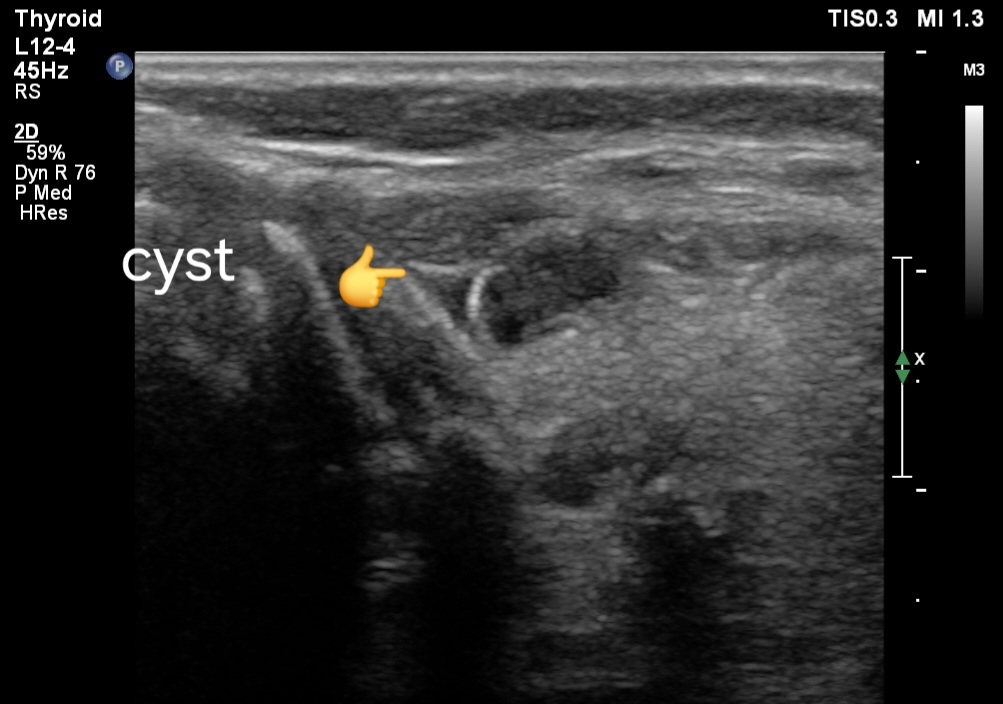

Multiple simple cysts of thyroid, ultrasound imaging

Ultrasound and Color Doppler Imaging Findings:

1. Ultrasound Findings:

- Cystic Appearance: The thyroid shows multiple small anechoic or hypoechoic areas corresponding to cysts, predominantly in the left lobe. These cysts are round or oval, with well-defined borders and no internal echoes if simple.

- Size:The cysts may vary in size but are typically small, often less than 1 cm in diameter.

- Internal Features: If the cysts are complex, they may contain internal debris, septations, or a mixture of solid and cystic components.

- Thyroid Parenchyma: The surrounding thyroid tissue may appear normal or show signs of background thyroid disease, such as Hashimoto's thyroiditis, which might present as a heterogeneous echotexture.